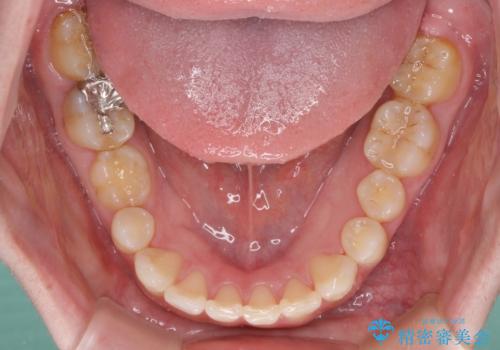

萌出が不十分な歯はインビザラインで引き出すことができないため、ワイヤー装置などの併用が必須となります。

今回は部分的にワイヤー矯正を用いましたが、右下の乳歯は全く動かなかったため、抜歯をした上でインプラントを埋入し、オールセラミッククラウンにて補綴治療を行いました。